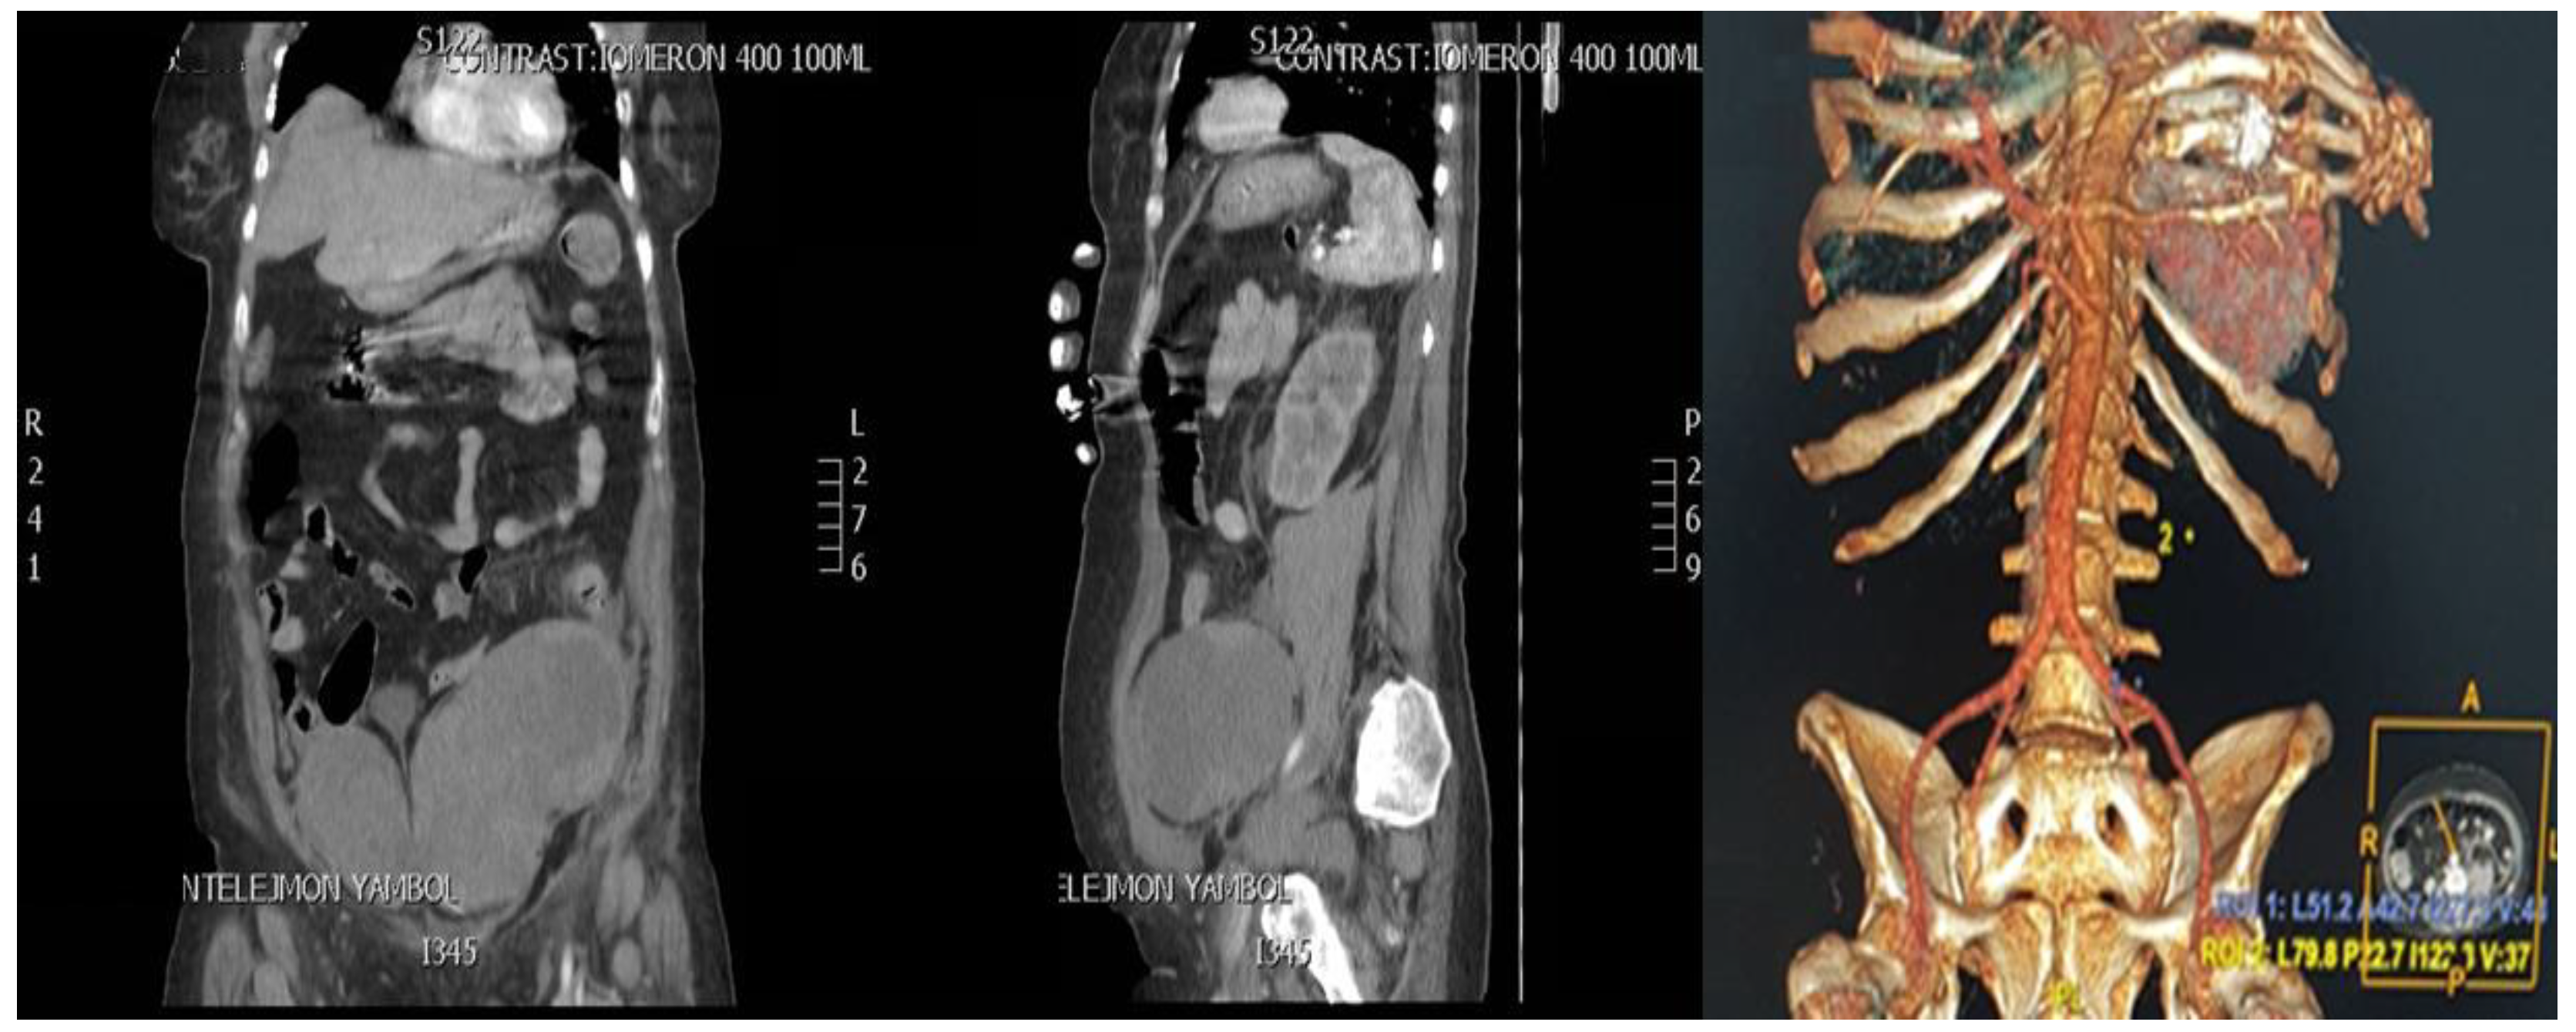

2. Case Presentation

2.3. CT Scan Report